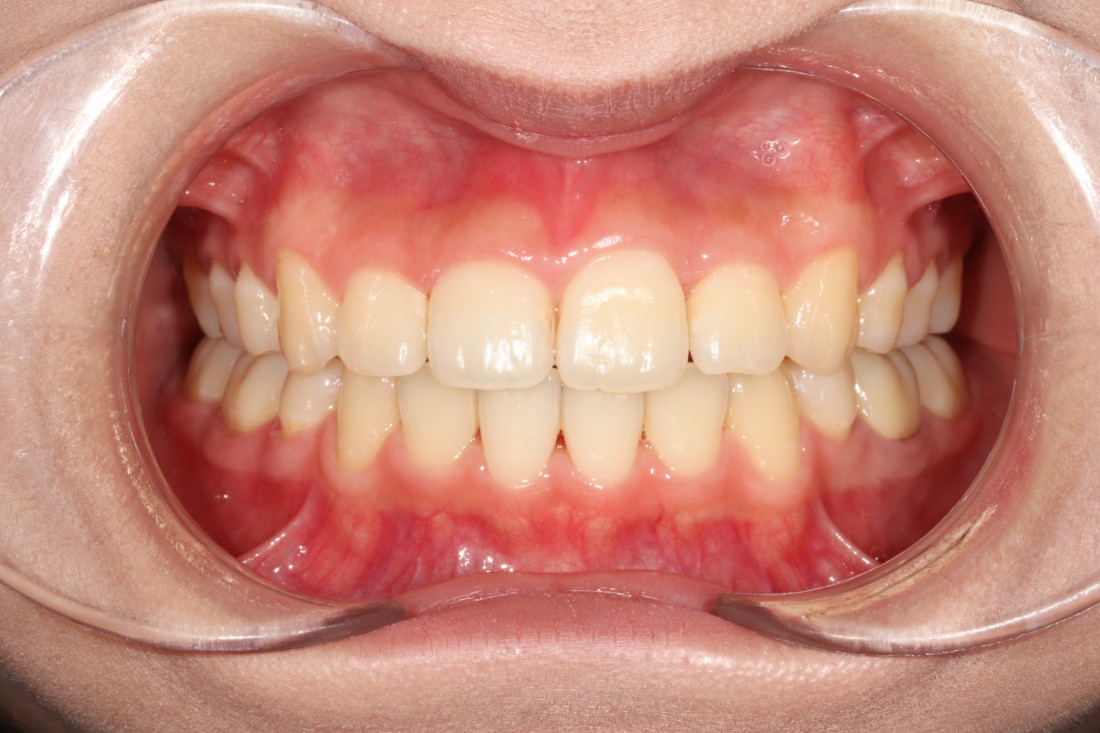

광주 성인 교정치과에서

충치치료와 교정진료를 동시에 받으신

성인 여성 환자분의 케이스입니다.

충치치료 전에는 은색 보철물이 있던 자리에

교정진료의 마무리와 동시에

치아색 보철물을 씌워서

치아교정 + 충치치료를 동시에 진행하였습니다.

광주 성인 치아교정의 경우

충치치료의 시기를 잘 판단하여

성공적인 진료를 완성할 수 있기 때문에

분과별 전문의가 협진하는

광주 성인 교정치과를 선택하시는 것이 좋습니다.